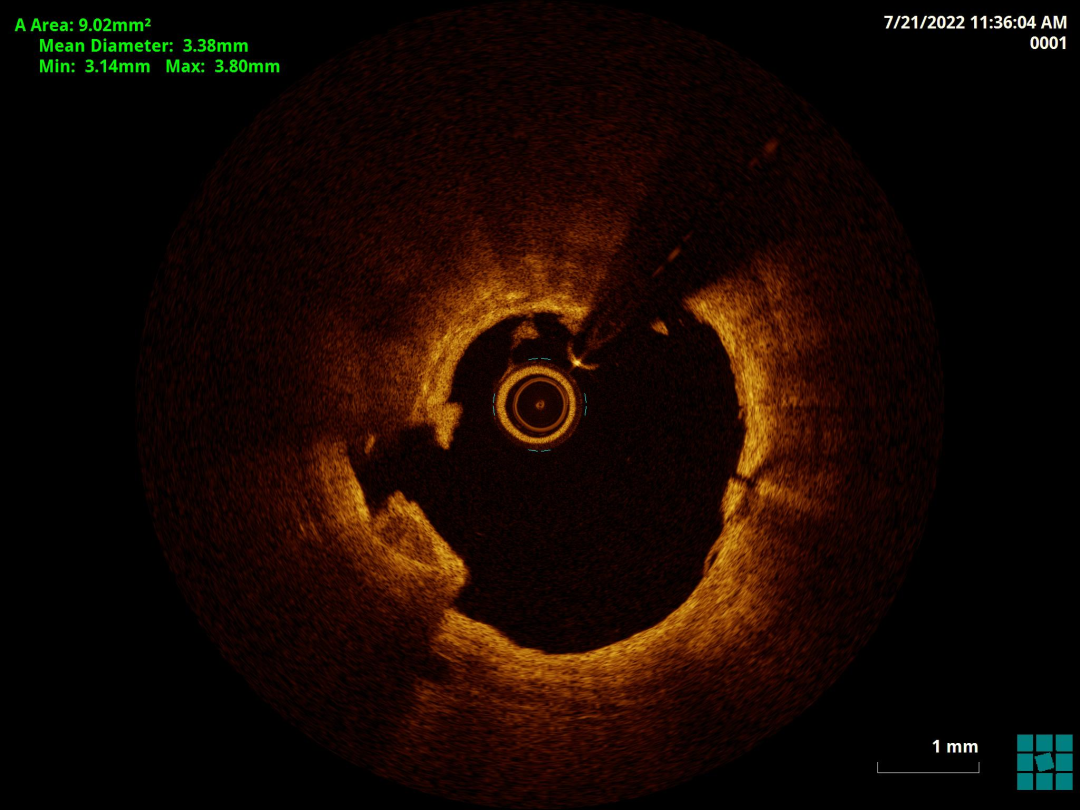

胡洵教授:术前Oct可见前降支中远段严重钙化病变,部分节段呈360度钙化环,最大钙化厚度0.8 mm,中段原支架最小支架面积3.9mm2,支架膨胀率63%,支架外可见明显钙化斑块,近段已用3.0shockwave冲击波球囊进行30次脉冲冲击,钙化病变处可见多处断裂,最深断裂处可达 0.55mm,使用3.0shockwave球囊于中段原支架膨胀不良处进行50次脉冲冲击,2.5shockwave球囊于中远段钙化病变处进行30次脉冲冲击,再次复查Oct可见中远段钙化环出现多处断裂,中段原支架膨胀不良处支架面积明显改善,在前降支远段植入2.5支架,中段原支架内予以3.0高压球囊扩张,近段植入3.5支架并用3.5高压球囊扩张,最后复查Oct见远段支架最小面积 4.21mm2,支架膨胀率75%,中段原支架最小支架面积5.08mm2,支架膨胀率75%,近段最小支架面积 10.20mm2,支架膨胀率85%。